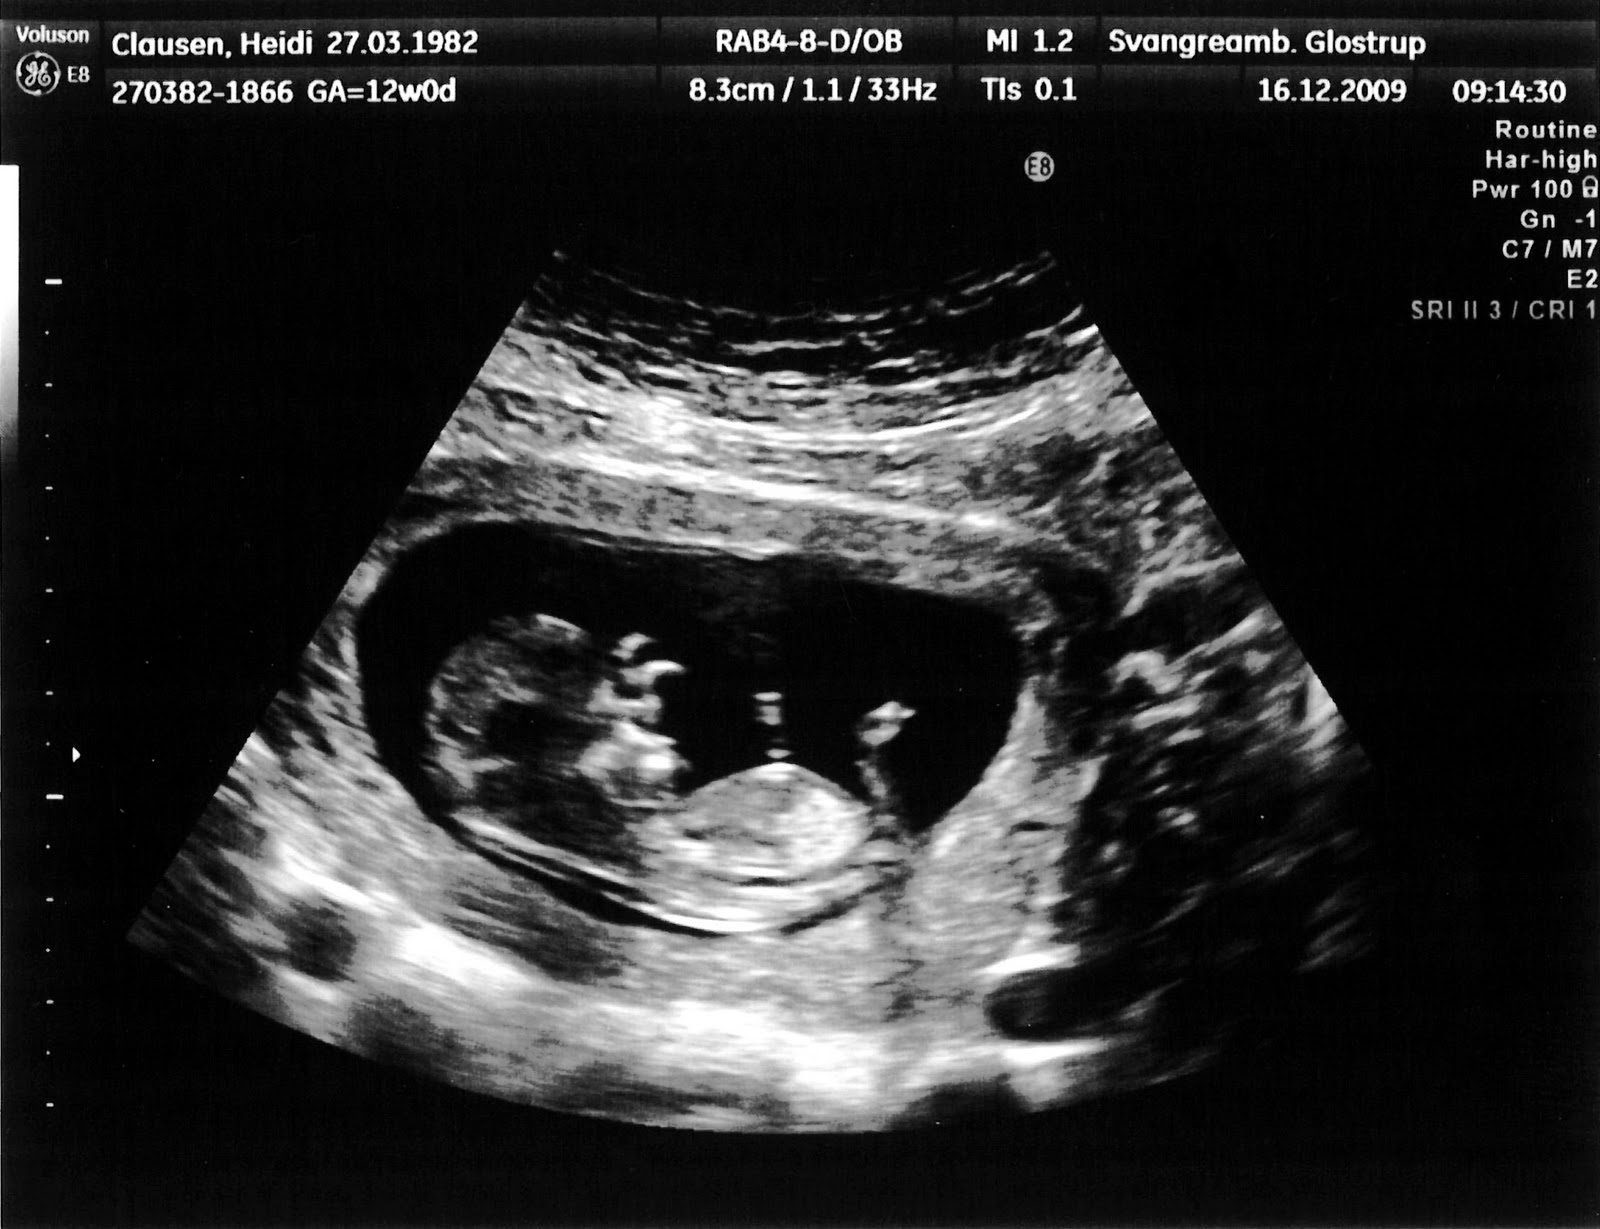

Jeg fik lavet nakkefoldsskanning selvom det først var meningen at jeg skulle have den lavet mellem jul og nytår, men lægen sagde at babyen lå helt rigtig og at vi lige så godt kunne lave undersøgelsen med det sammen. Alt gik rigtig fint, min risiko vurdering blev sat til 1:15687, så det er jo rigtig flot.

Jeg vidste faktisk slet ikke jeg skulle skannes, havde bare fået et brev hvor der stod at jeg skulle til samtale, så var lidt overrasket da hun sagde at vi lige snakkede lidt og så skannede hun mig derefter. Jeg sagde også til hende at Flemming ville blive rigtig skuffet nu hvor han ikke var med til nakkefoldsskanningen, men jeg fik 2 fine billeder med hjem.

Det var bare en rigtig god skanning, babyen lå og bevægede sig, det først minut bevægede den sig rigtig meget og derefter gad den ikke rigtig mere, men når jeg grinte og brugte mavemusklerne så lavede den små fine hop der inde, den var bare så fin. Jeg fik helt tåre i øjnene ville så gerne have haft Flemming med, men han må komme med næste gang.